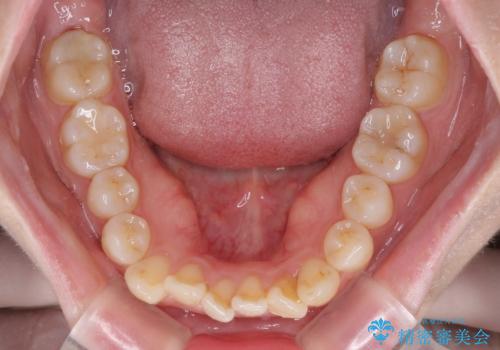

- 口元の突出感と口の閉じにくさを気にして来院された患者様です。

上下左右第一小臼歯4本を抜歯し、ワイヤー装置にて口元を引っ込めるよう矯正治療を行うこととしました。

2年~2年半が治療期間の目安でしたが、順調に治療が進み、1年9か月で満足のいく歯列となりました。